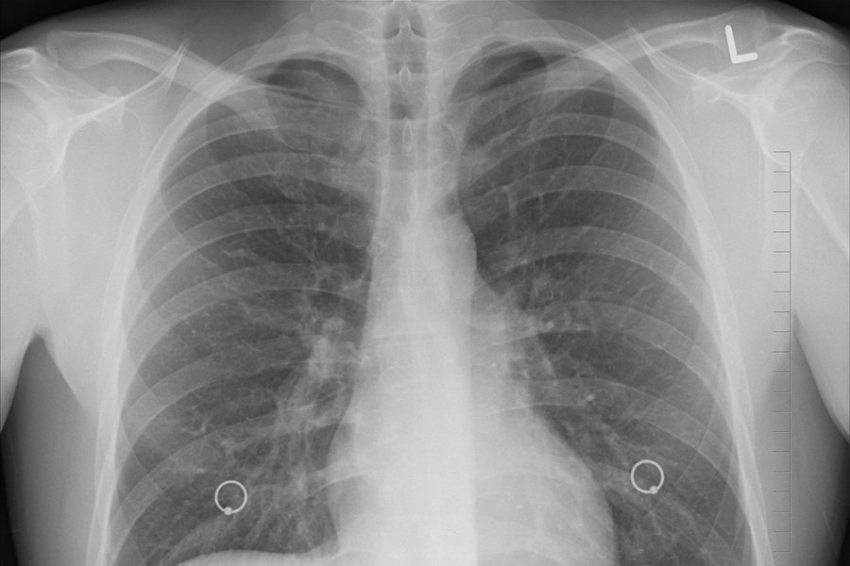

Командой из канадского Макгиллского университета установлено, что электронные сигареты со вкусом и ароматом ягод способны существенно ослабить естественную защиту легких, отчего организм теряет часть защитных сил для борьбы с инфекциями. Издание PNAS (Proceedings of the National Academy of Sciences) обнародовало результаты этой работы.

Результаты свидетельсвуют о том, что ряд химических веществ, выделяемых вейпами со вкусом ягод, оказывают «парализующее» влияние на иммунные клетки в легких. Негативному действию, в частности, подвергнута популяция клеток под названием альвеолярные макрофаги, они как раз и отвечают за выведение вредных частиц. Данный эффект приводит к росту восприимчивости организма к респираторным инфекциям.